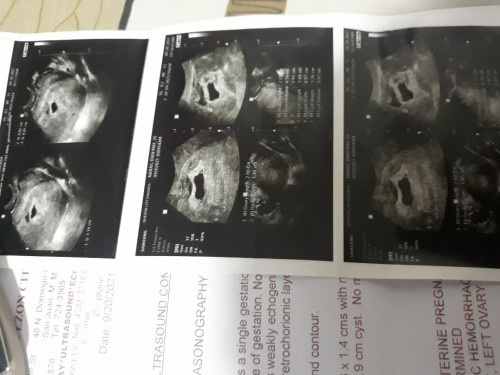

Magbasa panung 1st tranv ko po aug26,5w3d gestational sac lang ang mron,wla pang fetal pole,tpos ngaun dpat 9w na,sept20 6w2d dw,tpos gestational sac padin ang mron,wla padin baby,normal po b un,worried lang po tlga ako,

2nd transV ko na po ngaun,ang alam ko po 9w na,tpos po ung result ko now 6w2d,tpos wla padin bby,

Magbasa pasame po sa akin. yung bilang ko based sa last mens ko 9 weeks na ako pero sa tvs 6 weeks and 1 day pa lang at wala pang baby at heartbeat. pinabalik ako after two weeks at yun na may heartbeat na sya. 32 weeks pregnant ngayon at hirap na din. wooohh konting tiis na lang. don't stress yourself mommy, pray lang po. meron tlga ganyan minsan especially irregular ung regla mo.